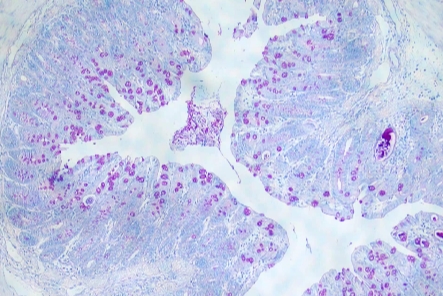

PAS糖原染色又稱過(guò)碘酸雪夫染色,糖原染色。

應(yīng)用:PAS染色在醫(yī)學(xué)和組織學(xué)研究中具有廣泛的應(yīng)用。它特別適用于識(shí)別中性粘液和杯狀細(xì)胞,這些細(xì)胞在呼吸道、消化道等黏膜組織中豐富存在。通過(guò)PAS染色,可以清晰地觀察到這些細(xì)胞內(nèi)的粘液分泌情況,對(duì)于診斷某些炎癥、感染以及腫瘤等疾病具有重要意義。此外,PAS染色還常用于研究糖原代謝相關(guān)疾病,如糖原貯積癥等,幫助醫(yī)生了解患者體內(nèi)糖原的分布和沉積情況,為制定治療方案提供依據(jù)。由于其操作簡(jiǎn)便、結(jié)果明確,PAS染色已成為病理學(xué)和組織學(xué)研究中不可或缺的技術(shù)之一。

糖原、中性粘液物質(zhì)、軟骨基質(zhì)、植物的真菌和細(xì)胞壁、上皮的基膜等均呈紫紅色,細(xì)胞核淺藍(lán)色。